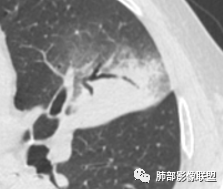

支气管稍扩张→有张力,GG0边缘清楚,局部有小叶间隔阻挡。

反思,恶性膨隆,远端空洞,强化坏死不均,里面血管似乎也是增粗,边界不清,似乎有侵犯。坏死还是边界不清。

1、团片状,实行密度区外观整体圆顿,位于上叶尖后段与下舌段区间。局部膨隆,但未见分叶,肿瘤多见。

4、支气管改变:上舌段支气管远段延入部分稍示僵硬。尖后段见分支支气管阻塞,恶性多见。

5、周围磨玻璃,3个月后逐渐转为密实,应符合当初附壁生长为主,且逐渐向实体成分转换。